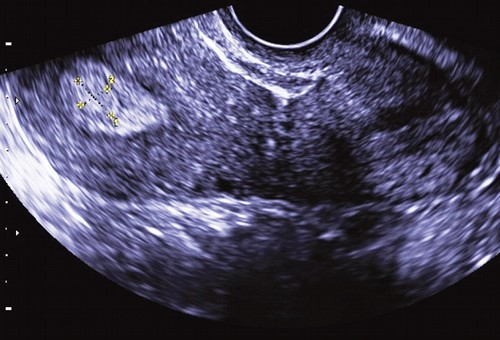

В то же время эхонегативное изображение жидкости (слизи) подчеркивает контуры эхопозитивного патологического образования, делая его хорошо заметным на эхограмме. Поскольку полип имеет внутрипросветный рост и частично обтурирует цервикальный канал, выше или ниже его может скапливаться слизь, что облегчает обнаружение патологического образования (рис. 2).

Рис. 2. Полип в просвете цервикального канала.